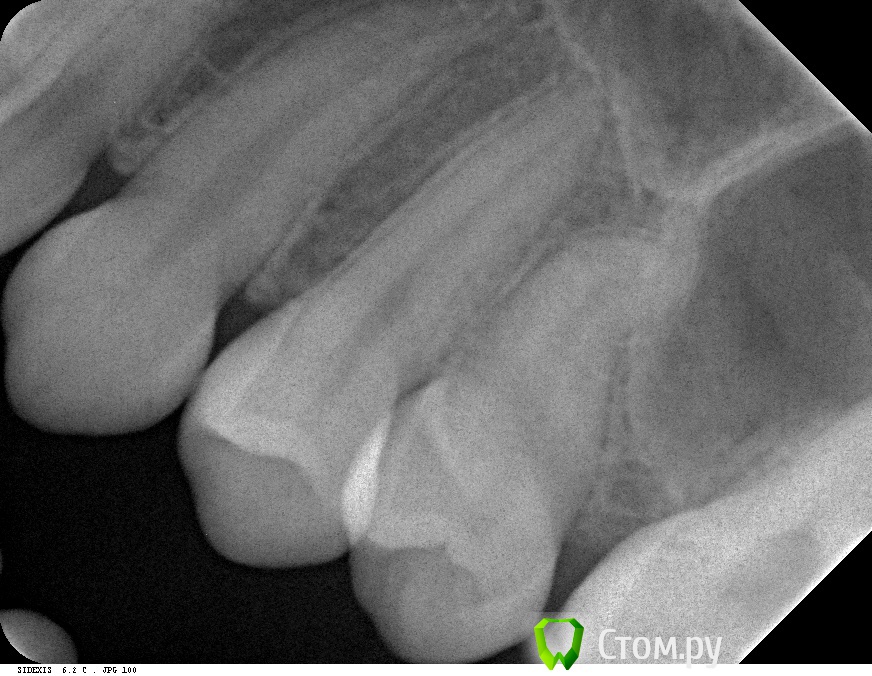

Ляйсан Опубликовано 30 декабря, 2013 Поделиться Опубликовано 30 декабря, 2013 Помогите определиться с диагнозом и дальнейшим планом лечения!Пациентка, 22 года, случайно после RVG обнаружилось вот такое новообразование, в области 25 зуба,зачаток 25 зуба отсутствует, 27 только-только начал прорезываться.Предполагаю что возможно это одонтома, как Вы думаете? Ссылка на комментарий

АнтонТЛТ Опубликовано 31 декабря, 2013 Поделиться Опубликовано 31 декабря, 2013 Думаю, гайморова пазуха Сделайте КТ или ОПТГ 6 Ссылка на комментарий

Petr_Off Опубликовано 31 декабря, 2013 Поделиться Опубликовано 31 декабря, 2013 А на Rg разве не 2.5 зуб? +1 за ОПГ или КТ. Однотома разве что мягкая, и то вроде как должны быть тени, а там полное просветление. Удачи. 1 Ссылка на комментарий

IvanK Опубликовано 31 декабря, 2013 Поделиться Опубликовано 31 декабря, 2013 Думаю, гайморова пазуха Сделайте КТ или ОПТГ+ 1такова анатомия 3 Ссылка на комментарий

samsonov Опубликовано 1 января, 2014 Поделиться Опубликовано 1 января, 2014 А на Rg разве не 2.5 зуб? +1 за ОПГ или КТ. Однотома разве что мягкая, и то вроде как должны быть тени, а там полное просветление. Удачи.Предположительно, автор описался, имея в виду 26. Ссылка на комментарий

Елена777 Опубликовано 26 января, 2014 Поделиться Опубликовано 26 января, 2014 М.б. И кератокиста. Сделать 3d, чтобы исключить бухту гайморовой, расрыть и делать эктомию, либо томию - по ситуации. Ссылка на комментарий

Василичdr Опубликовано 28 января, 2014 Поделиться Опубликовано 28 января, 2014 Либо 2.6 ранее удален,а это остаточная киста - подозрительная дивергенция корней рядомстоящих зубов Ссылка на комментарий